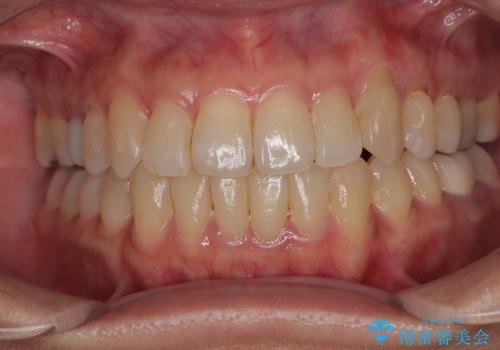

捻れて前に出ている前歯 ワイヤー装置での非抜歯矯正